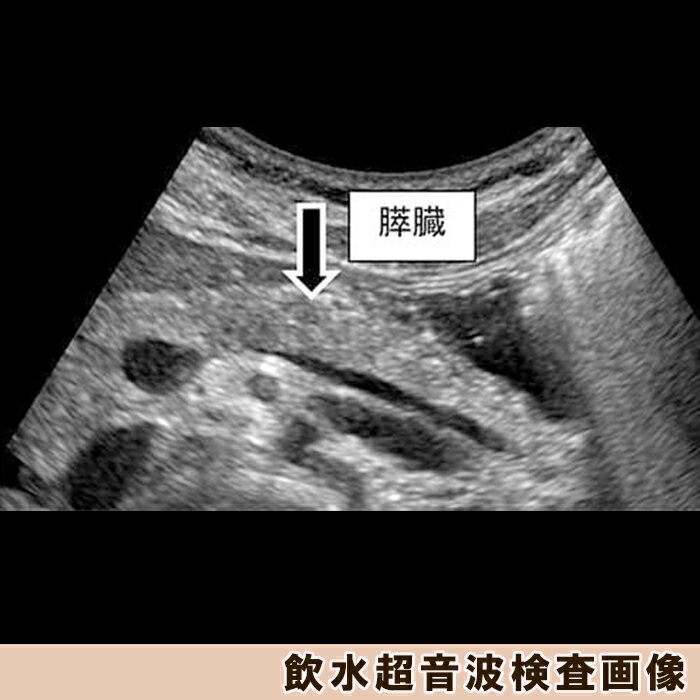

【ふるさと納税】【亀田クリニック人間ドック】アドバンスト2(膵臓)コース 1名様(1泊2日) [0670-0002]